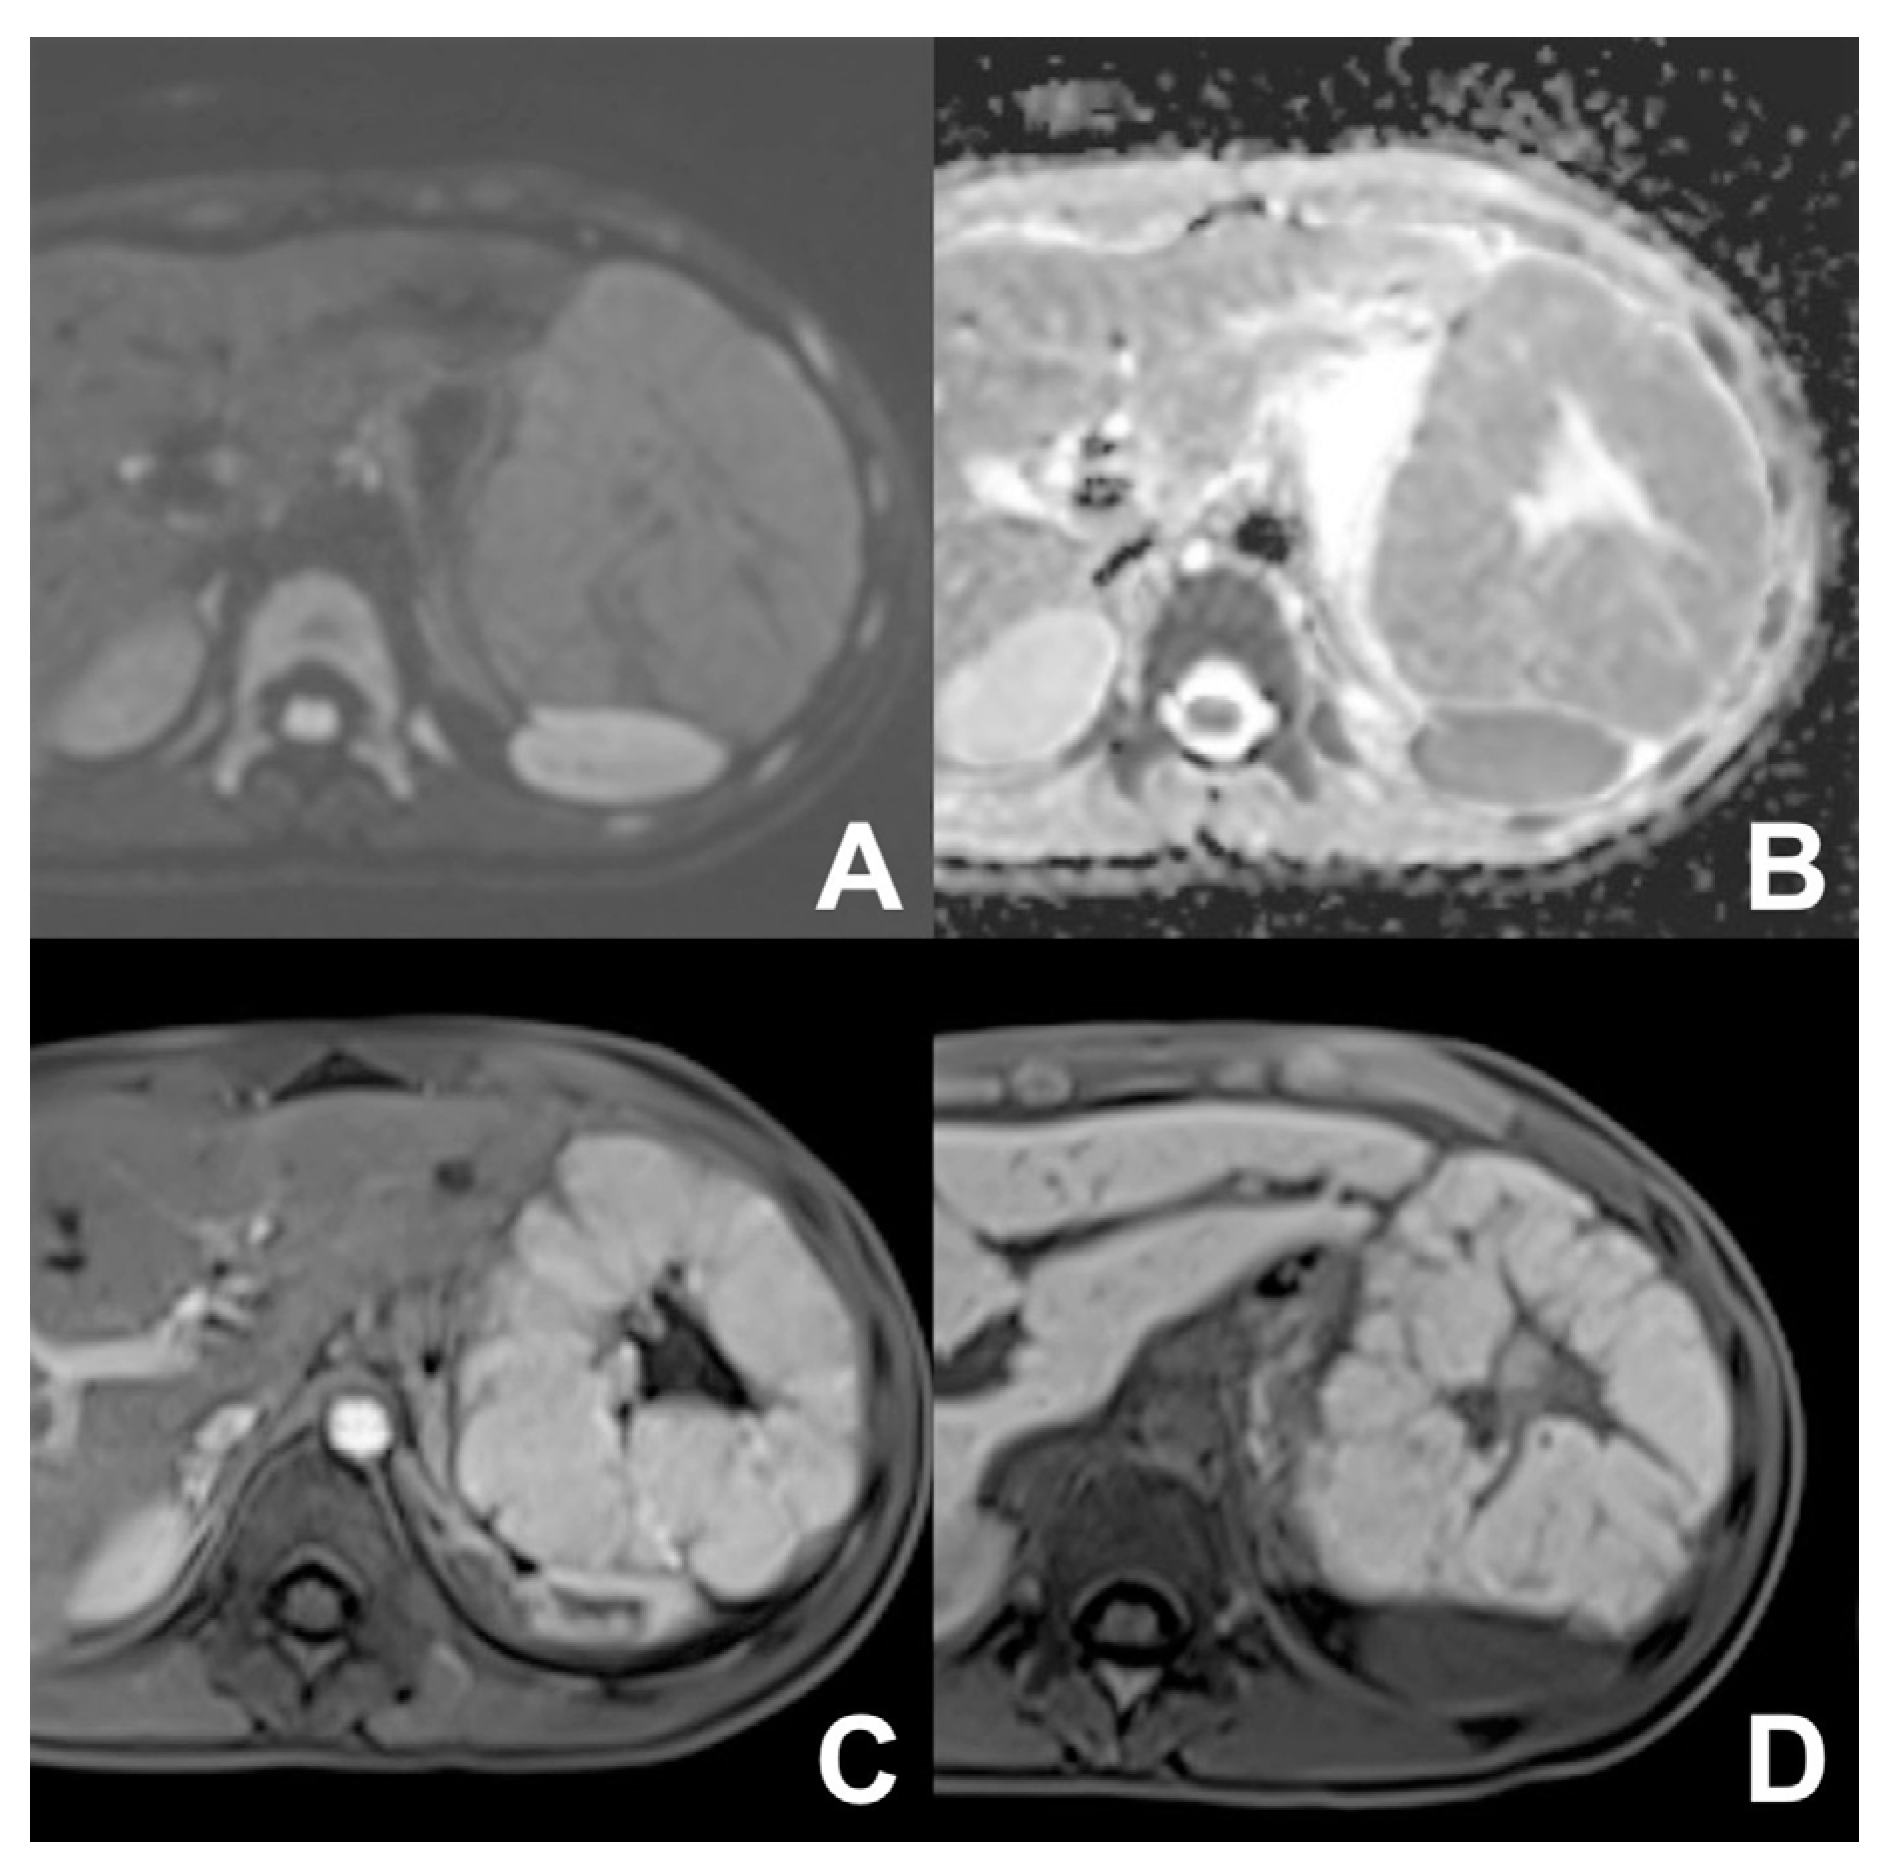

| DWI b 0–50–400–800 | AXIAL | -- | -- | Restricted diffusion most likely malignant | |

| GRE T1 IN/OUT | AXIAL | -- | -- | Steatosis | |

| GRE T1 3D DYNAMIC | AXIAL | PRE-ART 25″-PORTAL 70″-LATE 180″ | YES (if the lesion is hypervascular) | Benign hypervascular hepatocitic lesions appear hyperintense in HBP | |

| DWI b 0–50–400–800 | AXIAL | -- | -- | High signal in b 800 suspicious for HCC | |

| GRE T1 3D DYNAMIC | AXIAL | PRE-ART 25″-PORTAL 70″-LATE 180″ | YES (if the lesion shows atypical enhancement) | Hypointensity in HBP suspicious for HCC | |